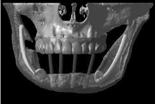

これは入れ歯を長年使い続けたことによって、歯を支える骨が溶けてしまっている患者さんのCTデータ三次元立体構築画像です(写真②)

入れ歯を長年使い続けていたために顎の骨の厚みがこんなに薄くなってしまいました

この写真を見てお分かりのように同世代の人でも入れ歯を使っている人と入れ歯を使っていない人では、

顎の骨の高さ厚みが違うのです。

顎の骨の高さ厚みが違うということは、つまり、

顔貌(かおかたち)も大きく違ってくるということです。

次に写真②をご覧下さい。

本来骨の高さの中央部分にあるはずの穴が上に向いて開いています。

つまり大きな神経や血管はとても大切なので、本来骨の奥深くに埋まって保護されているのです。

しかし、骨が大幅に溶けてしまって大きな神経が歯茎直下にまで出てきてしまっているのです。

歯があるときから神経が上にでているということは考えられませんので入れ歯を何年も使っていたために

本来骨の中にある神経のところまで骨吸収が起こったと考えられます。

神経が骨よりも上に出ていて入れ歯でこすられる状態ですので、

入れ歯を入れただけでも飛び上がるほどの痛さです。

よく、入れ歯を長年使われた方が、

「入れ歯を入れると、神経に触るように痛い」

「柔らかいものを咬んでも痛い」

こう訴えられる理由はここにあります。